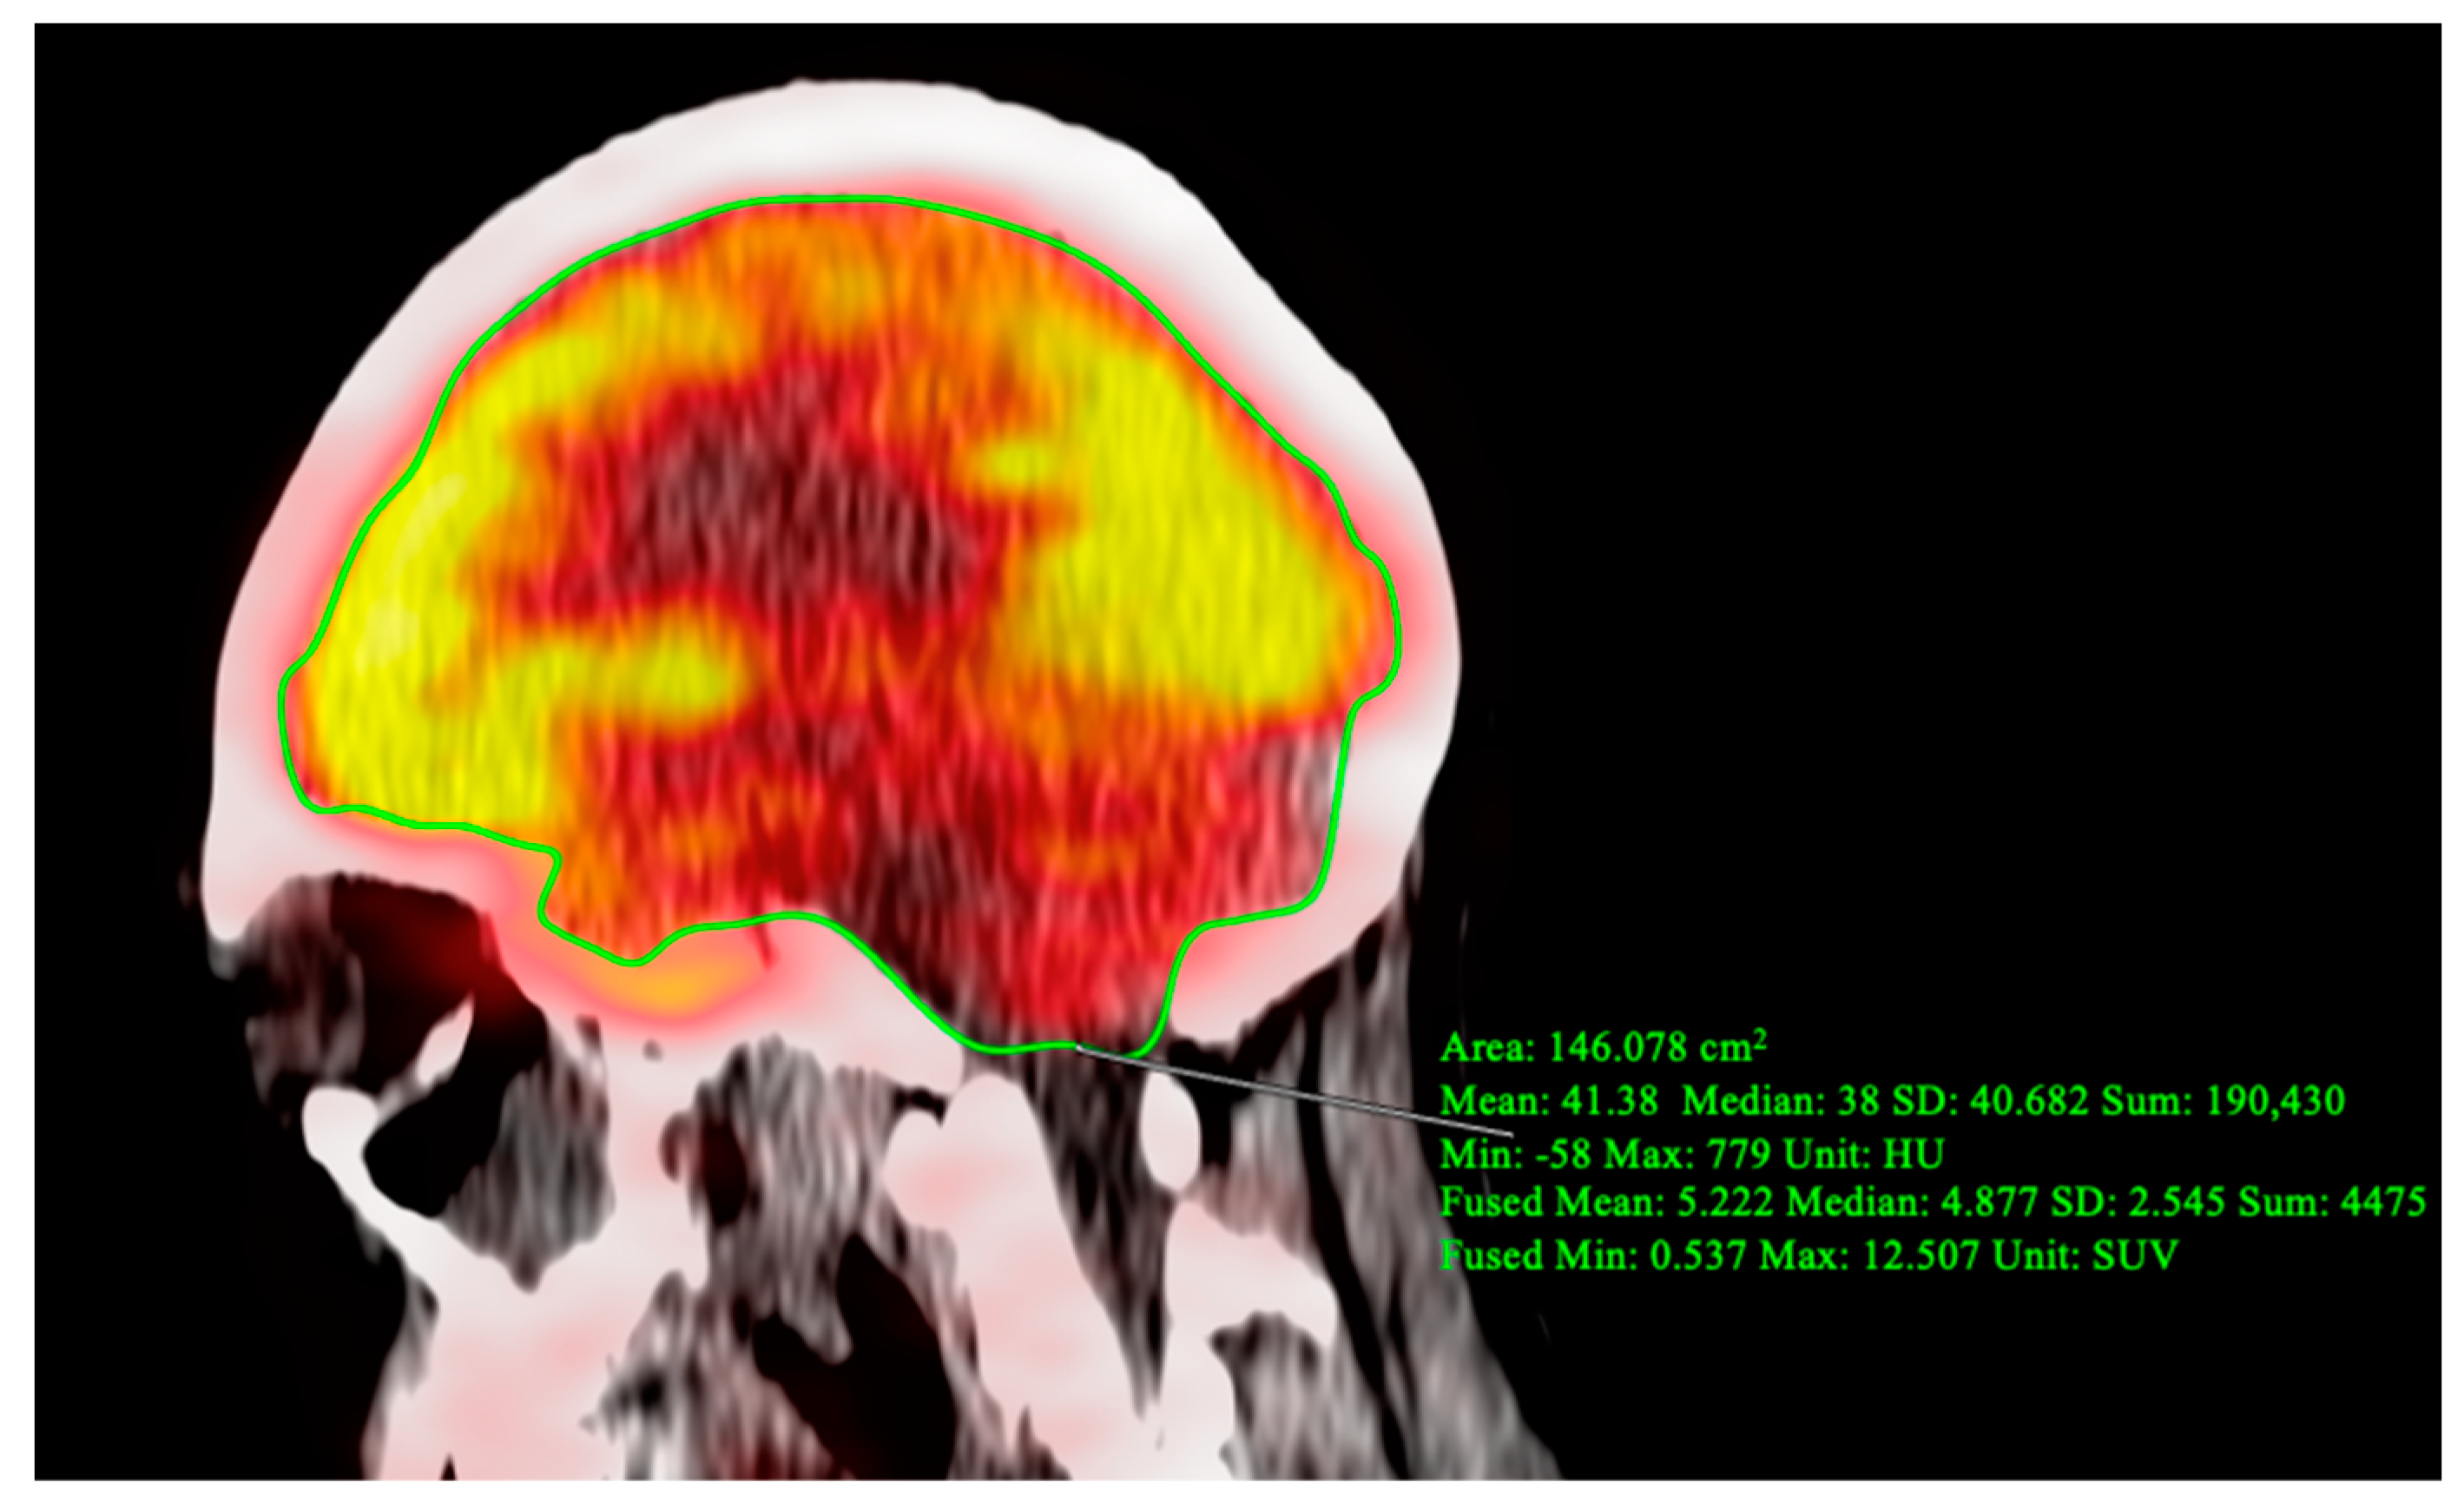

OsiriX MD was also utilized to perform global assessment of FDG uptake in the brain. CT-based segmentation of cerebral and cerebellar regions of interest were determined using precise anatomical landmarks visible on the fused PET/CT images. Specifically, regions were manually delineated on each sagittal slice (Figure 2). To analyze FDG regional uptake in the brain, quantitative regional analysis was conducted with MIMneuro version 7.1.5 (MIM Software, Inc., Cleveland, OH, USA) through validated methods [11,12]. PET data were mapped on a voxel-to-voxel basis to a standard brain template designed for comparison with an integrated anatomical brain atlas featuring predefined ROIs (Figure 3).

Figure 2.

Region of interest (ROI) delineated for the global assessment of the supratentorial and infratentorial regions of the brain on PET/CT image. For the drawn ROI slice, fused SUVmean = 5.222, indicating hypometabolism.

Brain FDG-PET/CT demonstrated decreased global brain metabolism, with an average SUVmean of 3.42 when compared to the average of 7.59 SUVmean for a cohort of 38 patients at increased cardiovascular risk. Furthermore, regional hypometabolism was observed, particularly in the brainstem (z score = −1.95), medial temporal lobe (z-score = −1.81), cerebellum (z–score = −2.13), hippocampus (z-score = −2.13), inferior frontal gyrus (z-score = −3.53), lateral orbital gyrus (z-score = −3.24), and putamen (z-score = −2.47).